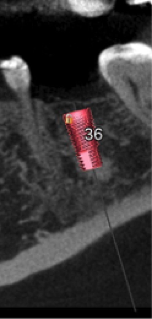

2. Virtual implant placement

Supply us with the implant brand and size and we will position it exactly to your specifications and in relation to the virtual final tooth position. We will send a written report for you to check and note any changes if needed. We will not make the guide until you are 100% satisfied with the virtual placement. Alternatively use free software to plan the case yourself and send us the plan file and we can make the guide from that.

4. Select guide type

5. Guide fabrication

We use state of the art FDA and TGA approved, fully tested and calibrated 3D printing machines and materials for our surgical guides. You will receive a perfectly fitting sturdy guide with drill tubes precision fitted ready for use. All guides are manufactured in Sydney, Australia at our own dedicated facility so fast turnaround is always guaranteed. Rush orders are usually not an issue.

We will supply a drill guide with drill tubes suitable for your selected type of guide.

Anatomy of an Implaguide

AUTO PILOT

FINAL DRILL

FULLY GUIDED